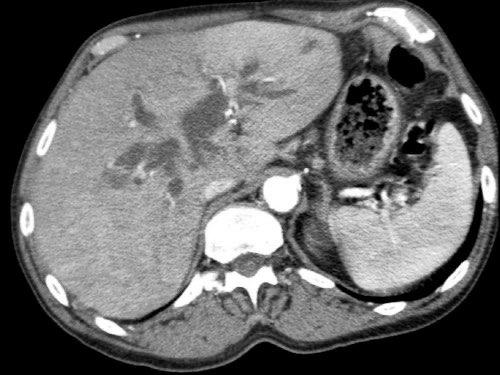

CT axial cho thấy:

- Khối u ở thân tụy (đầu mũi tên trắng).

- Tiếp xúc khu trú < 90º với động mạch mạc treo tràng trên (SMA).

- Tiếp xúc rộng hơn từ 90º – 180º với SMV, SMV bị hẹp nhẹ và biến dạng (mũi tên vàng).

- Giãn ống tụy